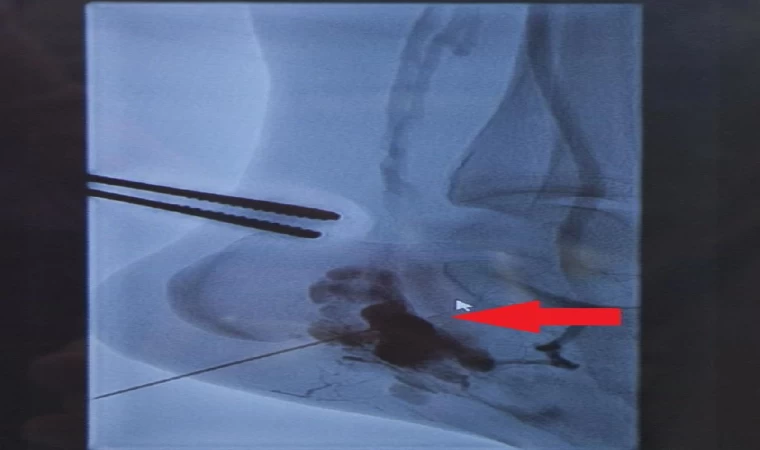

Koç Üniversitesi Tıp Fakültesi Hastanesi Pediatrik ve Konjenital Kalp ve Damar Cerrahisi Bölüm Başkanı Prof. Dr. Kalangos, 2021 yılında kendisine ulaştığında Merve’nin yürüyemez halde olduğunu söyleyerek şu bilgileri verdi: “Ayakta nükseden bir damar tümörü şikayeti vardı. Birkaç kez ameliyat olmuş, skleroterapi (varis tedavisi) görmüş ama faydası olmamış. Kızımız artık bacağını kurtarma endişesiyle bize gelmişti ve yürüme performansı yüzde 80 azalmış durumdaydı. Ayak parmak kemiklerinde de deformasyon vardı. Bir ampütasyon tehlikesiyle de karşı karşıyaydık. Ortopedi ve estetik, plastik, rekonstrüktif cerrahi ekibi ile hep beraber, onun sol ayağının etrafında toplandık. Kızımıza radikal bir tedavi yapıp ayağını kurtarma ameliyatını gerçekleştirdik. Oradaki damarsal kitleyi tamamıyla çıkardık. Daha sonra da ortopedik cerrahlar gerekli kemik düzeltmelerini yaptılar. Plastik cerrahlar da aynı anda devreye girip oradaki duyusal durumu düzeltmek için sinir nakli ameliyatı gerçekleştirdiler"

AVM’nin kendi başına çok nadir görülen damarsal yapılar olduğunu kaydeden Prof. Dr. Kalangos, ayak topuğunda görülmesine ise literatürde hiç rastlamadıklarını kaydetti. Tüm dünyadan buna benzer yüzlerce zor vakayı ameliyat ettiğini anlatan Prof. Dr. Kalangos, Merve’nin durumunun kendisinin bile şaşırttığını söyleyerek “Bu tümörün ayak konumunda olması çok çok çok nadir, neredeyse hiç yok gibi. O damarsal oluşumun üzerine sürekli bastığı bir konumda; sürekli ağırlık altında olduğu için patlama tehlikesi vardı. Kan bacaktaki kılcal damarlara neredeyse hiç gitmiyordu. Ben 36 yıllık cerrahlık kariyerimde ilk defa bu konumda görüyorum bu hastalığı ki bu alanda bu tümörleri dünyada en çok yapan cerrahlardan biriyim. Şimdi onu 2 yıl sonra böyle karşımda yürüyerek görmek, benim için en büyük hediye" diye konuştu.